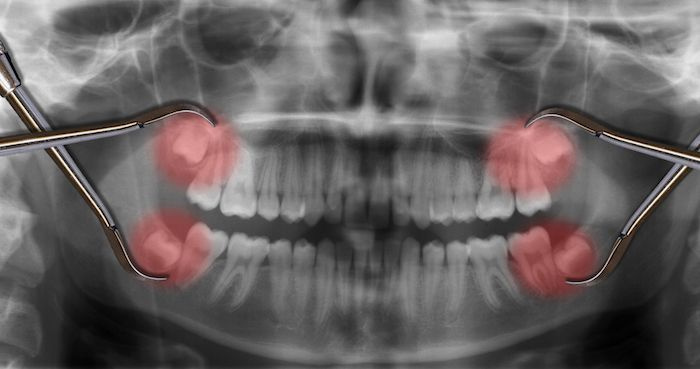

La gingivitis es la inflamación de las encías debido a la acumulación del sarro entre diente y encía provocando la inflamación de las mismas y el sangrado. Si la enfermedad no se resuelve a tiempo y la infección sigue su evolución puede derivar en una periodontitis. En esta fase las encías se retraen y puede dañar el hueso que soporta el diente y favorecer su pérdida.